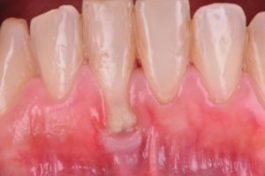

Esta paciente acude para consultar la exposición de la raíz que presenta en los incisivos inferiores. Ha estado vigilando la situación durante años, pero ella considera que ha aumentado más.

El incisivo inferior presenta una “recesión” (retracción de la encía) de 6mm. Esto no supone un motivo de pérdida dentaria,(Foto 1) pero la paciente no consigue mantener una adecuada higiene oral en la zona por molestia al existir ausencia de encía queratinizada (encía capaz de soportar el cepillado sin dolor).

Foto 1